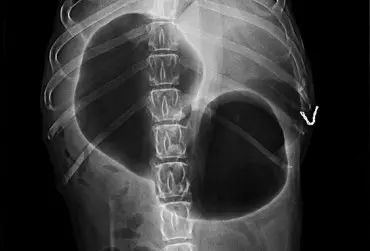

Rozszerzenie i skręt żołądka u psów

Skręt żołądka to hasło, które spędza sen z powiek znakomitej części opiekunów dużych i olbrzymich ras. Zwłaszcza w gronie właścicieli molosów jest to temat, który notorycznie pojawia się zarówno na forach internetowych, jak i w rozmowach na żywo. Głośno wypowiedziany, zawsze wywołuje spore emocje, a wszystko za sprawą realnego zagrożenia życia, jakie za sobą niesie, oraz często nierównej walki z czasem.